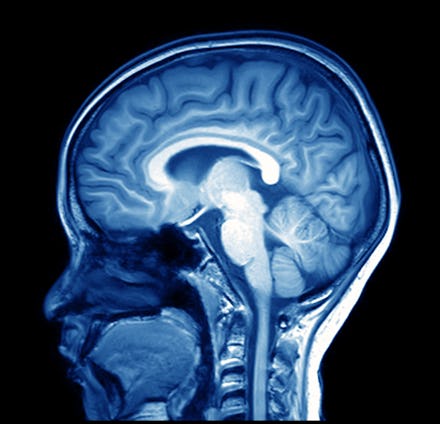

Scientists at Carnegie Mellon University read human thoughts by combining photos of the brain collected from MRI devices with machine learning algorithms. Machine learning is a subset of artificial intelligence that allows machines to learn from data themselves, without being explicitly programmed.